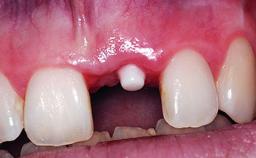

A healthy 37-year-old female patient was referred for a consultation on the replacement of missing tooth 21 with an implant-supported restoration. She stated that several years previously the tooth had been traumatically avulsed following a motor vehicle accident. The tooth was replaced with a three-unit fixed partial denture (FPD) immediately afterwards. Over time, she became disillusioned with the FPD and looked for a different option, including orthodontic therapy. She presented still in her orthodontic appliances, with the pontic sectioned free from the FPD but attached to the archwire. Her orthodontist felt that orthodontic treatment had been successfully completed, but nevertheless referred her before removing the appliances in case adjustments were necessary.